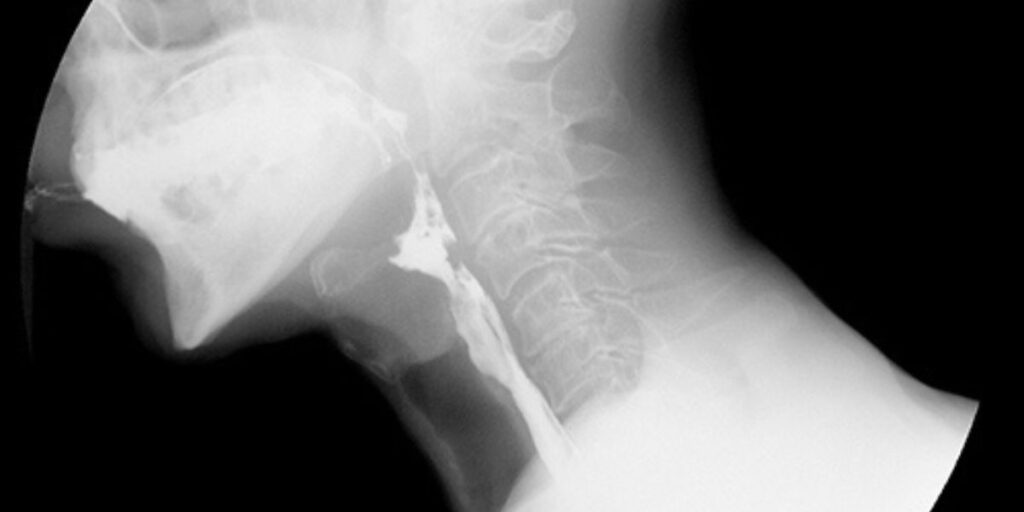

L’Esame RX Esofago con doppio contrasto è una tecnica radiologica avanzata che utilizza un mezzo di contrasto per visualizzare chiaramente le pareti dell’esofago. Questa procedura prevede l’assunzione di una soluzione di contrasto negativo, seguita dall’introduzione di aria, che permette di ottenere un’immagine nitida e dettagliata della superficie interna dell’esofago. Tale metodo è particolarmente utile per identificare lesioni e anomalie che potrebbero non essere visibili con altre tecniche diagnostiche.

Durante l’esecuzione dell’Esame RX Esofago con doppio contrasto, il paziente assume una soluzione di contrasto che aderisce alle pareti dell’esofago, rendendole visibili ai raggi X. Successivamente, viene introdotta aria nell’esofago tramite un sottile tubo, creando un contrasto che permette di osservare con chiarezza le strutture esofagee. Il radiologo acquisisce diverse immagini in varie posizioni del paziente per ottenere una visione completa dell’esofago e individuare eventuali anomalie o patologie.